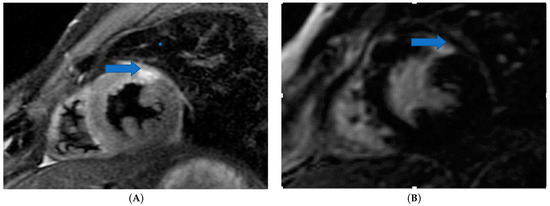

4.3. Myocardial Ischemia Assessment

4.4. Non-Invasive Coronary Artery Evaluation